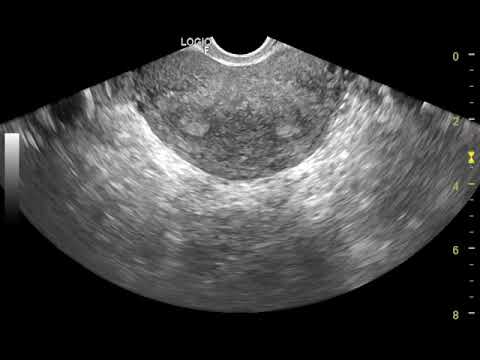

- ультразвуковое исследование органов малого таза;

На ультразвуковом исследовании органов полости малого таза матка определяется в виде седла. Но этот метод не всегда позволяет выявить данный порок. Так, при незначительной деформации матки не всегда визуализируется седловидная матка. Для более точной диагностики ультразвуковое исследование лучше проводить во вторую фазу цикла. Объясняется это тем, что толщина эндометрия (ткани, выстилающей полость матки) достигает максимального значения. Именно это и позволяет доктору увидеть деформированную полость матки.